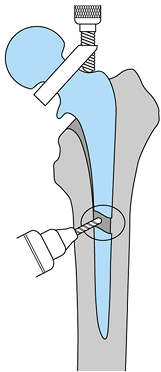

solution is a constrained acetabular liner. A constrained liner has

polyethylene that extends past the midpoint, or maximal circumference

of the femoral head (Fig. 106.5). The femoral

head must be forced into the polyethylene to reduce the hip and then a

locking ring locks the head in place. This design decreases hip motion

and increases the stress necessary to dislocate the hip. However, the

strain that occurs when this device prevents dislocation is transferred

to the component bone interface and may lead to early loosening.

Another concern is a higher rate of wear. The use of these devices

should be limited to situations without other good alternatives (35).

![]() |

|

Figure 106.5. A: Bipolar constrained liner, which is inserted into a metal-backed shell. B:

Motion is decreased with a constrained design, and stress at interfaces is increased. (Reprinted from Cameron HH. Modified Cups. The Orthopedic Clinics of North America 1998;28:277, with permission.) |